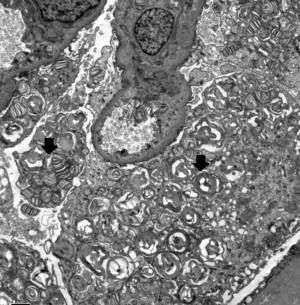

Electron microscopy revealed obvious vacuolar degeneration of capillary endothelial cells, typical electron-dense multilamellar inclusions and zebra bodies and an increase in secondary lysosomes in the cytoplasm of epithelial cells (Figure 4).

This report shows an important point regarding kidney biopsy. The kidney is one of the main target organs of FD, and renal pathological examination has been widely carried out. Although the proband’s kidney specimen demonstrated a mildly abnormal appearance under light microscopy examination, electron microscopy clearly demonstrated lamellated myelin structures and confirmed the diagnosis of typical FD (26). If the characteristic changes of renal pathology can be fully understood, when they are combined with clinical multisystem performance, the diagnosis rate of FD can be greatly improved. Some clinically normal heterozygous females have typical kidney biopsy findings (27). GLA activity when measured in blood may not reflect the true level of the enzyme activity in the affected organs. Therefore the critical threshold of GLA activity is hard to be determined (28). This implies that biopsy of the involved organ could help us identify the extent of FD and start therapy accordingly.